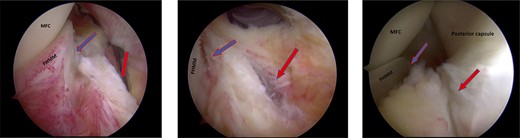

Trans-notch view of the posteromedial compartment of the left knee showing the blue arrow indicates the first lesion at the meniscosynovial junction of the red-red zone, and the red arrow indicates the second tear at the meniscocapsular attachment.

Standard diagnostic arthroscopy confirmed the presence of an intact ACL graft. Trans-notch arthroscopic visualization revealed a double meniscus ramp lesion (Figs 2–5). It was noted that the tear located at the meniscosynovial junction in the red-red zone of the PHMM was associated with MTL disruption, while the second tear was more posteriorly situated at the meniscocapsular junction and was associated with meniscocapsular attachment disruption. Probing of the meniscus resulted in its significant displacement.